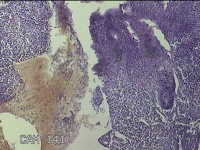

性别

女

年龄

16岁

临床诊断

子宫异常出血 慢性宫颈炎

一般病史

阴道出血近一个月。

标本名称

子宫腔内膜

大体所见

灰白暗红色不规则碎组织3.5x1.8x0.8cm一堆。